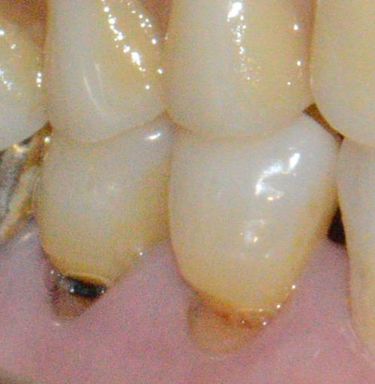

안녕하세요 목동안치과의 안상우 원장입니다.오늘은 치아 사이에 음식물이 끼는 원인과 이를 예방하는 방법에 대해서 알아보고자 합니다.치아 사이에 음식물이 끼는 원인은 무엇일까요?치아 사이에 음식물이 끼는 이유는 거기에 공간이 있기 때문입니다.그럼 치아 사이에 공간이 생기는 원인이 무엇일까요?그 원인에 대해서 알아보려고 합니다.우선적으로 충치등으로 인해서 치아 사이에 공간이 생기게 되면 음식물이 낄수 있습니다.치아의 인접면은 관리를 잘 안하게 되면 충치가 쉽게 생길수 있는 부위에요.또한 마모증으로 인해서 치아의 옆면이 이런식을 깎여 나가게 되어도 충치가 생길 수 있습니다.이런원인으로 인한 음식물의 끼임은 충치가 있는 부위의 충치를 제거하고 원래 치아 처럼 수복을 시켜주면 됩니다.다음으로는 치주질환이 있어서 치아 자체가 움직이게 됨으로써 생기는 공간이 있을수 있습니다.치아가 흔들리는 원인은 여러가지가 있을수 있는데 우선적으로 치아를 고정하고 있는 치조골이 약해 짐으로써 흔들릴수 있습니다.치아가 흔들리게 되면 사이에 공간이 생기게 되는것이고 음식물이 끼게 되는것 입니다.이런경우 잇몸에 염증을 줄이기 위해서 잇몸치료를 해줘야 합니다.다음에 치아가 흔들리지 않도록 교합간섭등을 조절하고 치아에 가해지는 힘을 줄여야 해요.어떤 분들은 이런 치아 사이를 그냥 메꾸면 되지 않냐고 하시는 분들고 계세요.치아 사이를 그냥 메꾸게 되면 일시적으로 음식물이 잘 들어가지 않겠지만 한번 들어간 음식물이 빠져나오지 못해서 결과적으로 잇몸에 염증을 유발하게 됩니다.또한 치아가 다시 흔들리게 되면 공간이 넓어지게 될수도 있어요.이런 치아의 흔들림이 있거나 해서 음식물이 자꾸 끼게 된다면 치아 자체를 열결해서 씌우게 되면 치아의 흔들림을 줄이는 동시에 공간을 메꿀수 있습니다.크라운치료라고 하는 치료입니다.음식물이 들어가는 방향에 대해서 알아 볼껀데요음실물은 두가지 방향으로 끼게 됩니다. 옆과 위쪽 방향입니다.음식은 치아의 옆면으로 들어 갈수 있습니다 .젊을때는 치아가 촘촘하게 잘 있지만 나이가 들면서 잇몸뼈가 점차 내려가게 되면 치아 사이에 공간이 생깁니다.음식을 먹게 되면 이 부위로 음식물이 들어갈수 있어요.이렇게 들어가는 음식물은 비정상적인 것이 아니라 자연스러운 현상입니다.이런식의 음식물은 치실이나 치간 칫솔로 제거해 줘야 합니다.다른방향인 위에서 음식물이 들어가는 경우가 있어요위에 끼는 음식물의 경우에는 치아의 이동이나 충치등으로 인해서 치아 사이에 공간이 생겨서 끼게 됩니다.이런경우에도 통증이 없다면 관리를 하면서 사용할수 있습니다.하지만 위에서 음식물이 들어가서 통증이 있다면 공간을 메꾸기 위해서 치료를 해야 합니다.통증이 있다는것은 음식물이 위에서 끼어서 잇몸을 누르고 있다는 의미이거든요이런 상태는 나중에 치주질환을 유발할수 있어요.아까 말씀드린 인접면을 치과재료로 메꾸거나 보철치료로 치아 자체를 씌워줄수 있어요.치아 사이에 공간이 있는지는 어떻게 알수 있을까요?치아 사이에 공간이 있는지 알아보기 위해서는 치실을 사용해 보시면 되요.치실을 사용해서 치아 사이를 왔다 갔다 했을때 딸깍딸깍 소리가 나면 치아가 정상적으로 닿고 있다는것입니다.치실을 사용했을때 치아 사이가 저항감이 없이 훌렁훌렁 통과 한다면 치아사이가 닿고 있지 않다는것이기 때문에 치료가 필요할수 있어요.치아 사이에 음식물이 자주 낀다고 생각되신다면 치실을 이용해서 치아가 사이에 공간이 있는지 확인해 보시고 필요하다면 치과에서 진료를 받아 보세요.